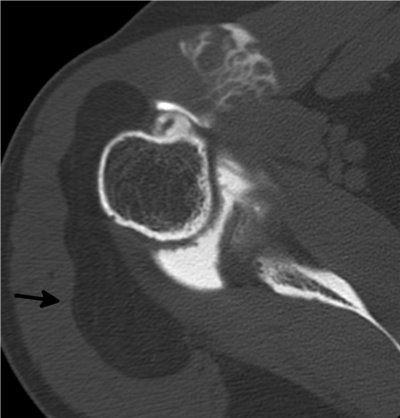

Capsulite rétractile arthrographie (images 1 et 2)

Arthroscanner correspondant (images 3 et 4)